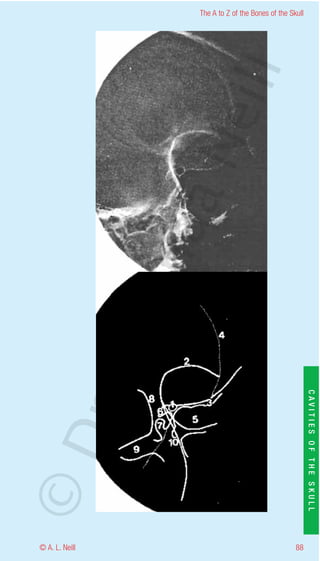

The A to Z of the Bones of the Skull

Optic Cavity Lateral / oblique

eill

radiology

1      Optic foramen

2      Supraorbital ridge

3      Sphenoid ridge

aN

4      Frontal bone

5      Sphenoid sinus (note clear no fluid lines as with sinusitis)

6      Anterior clinoid process

7      Posterior clinoid process

8      Frontal process of zygoma

9      Zygomatic arch

nd

10     Lateral border of greater wing of the sphenoid

ma

rA

CAVITIES OF THE SKULL

©D

87                                                           © A. L. Neill